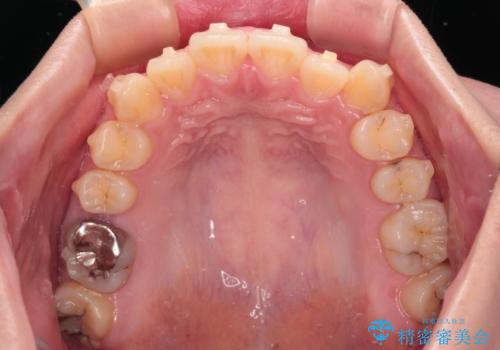

- 左右の八重歯を気にして来院された患者様です。

歯列としてはインビザラインでもワイヤー矯正でも対応できるものでしたが、インビザラインによる治療を希望されていました。

上顎の八重歯改善にインビザラインでは時間のかかってしまう可能性があり、更には口元が治療前よりも突出してしまう可能性があったため、補助装置により八重歯を事前に引き込んでおくことで、インビザラインによる治療をスムーズに行えるように計画しました。

補助装置を使用したことで、口元が突出することもなく、スムーズに仕上げることができました。